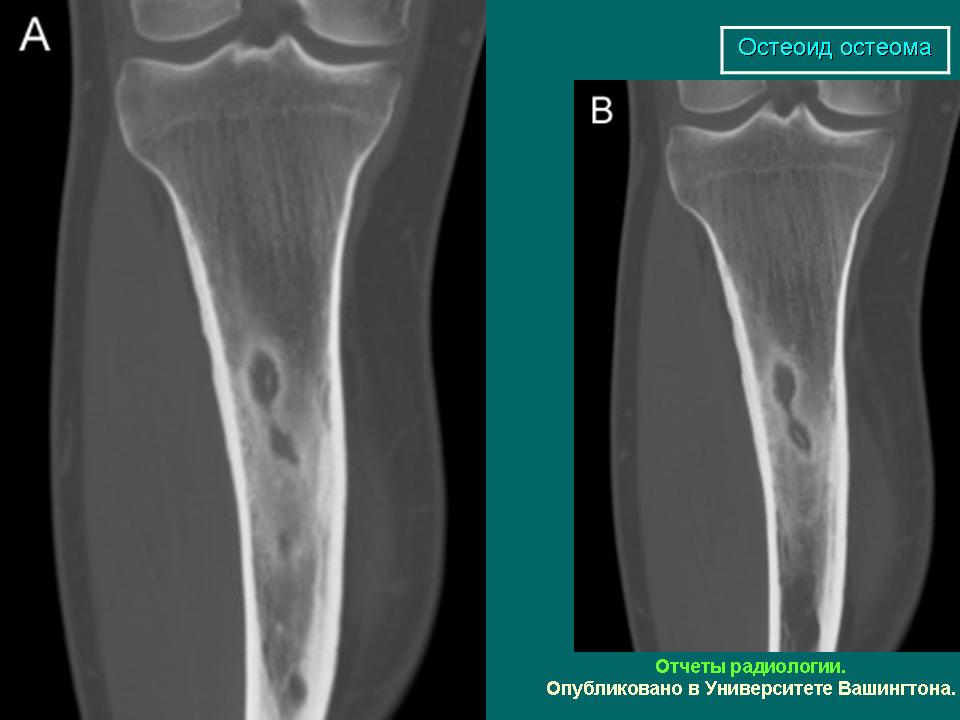

Доктор Сегаль. Удаление остеоидной остеомы.

Лечение остеоидной остеомы фокусированным ультразвуком (ФУЗ-МРТ) без операций и побочных эффектов.